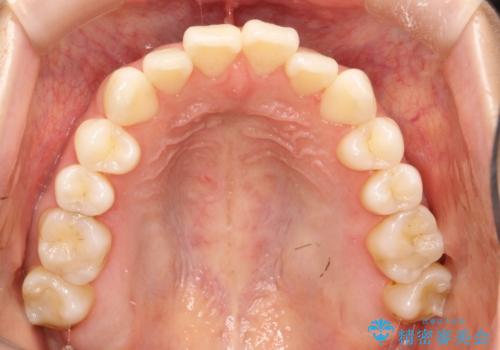

軽度の前歯のガタガタをインビザラインでの目立たない矯正

- 前歯のガタガタを主訴に来院されました。

軽度であったため、枚数制限のあるタイプのインビザラインのプランで治療することとしました。